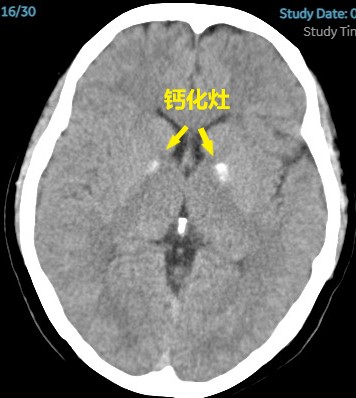

患者头颅CT提示基底节和反射冠多发小斑片缺血灶,双侧基底节钙化灶,排除脑桥小脑角处占位性疾病,骨窗排除中耳炎等疾病。电测听提示双耳听力在20-30分贝之间。